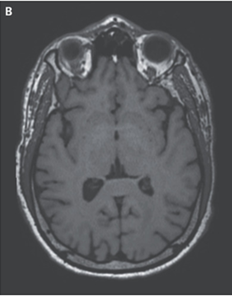

EDTAの静脈内投与による治療が6ヵ月間行われ、患者の症状は軽快し、MRI上の異常所見も解消された。